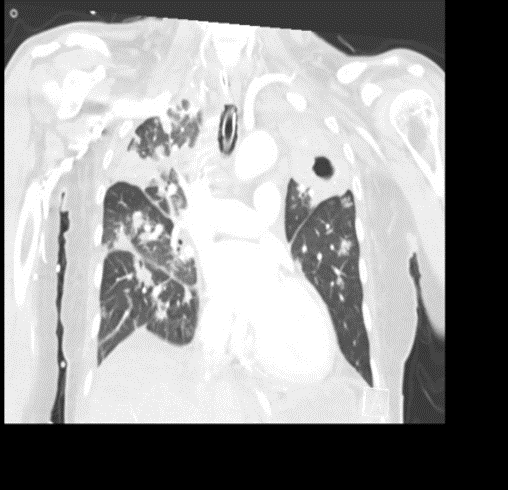

CASE 5 –A 57-year-old woman presented to the emergency department with fevers, cough and night sweats and recent weight loss. She arrived in Australia from Philippines 5 days previously. In the ED she had significant respiratory distress requiring high flow oxygen and subsequent intubation and ventilation as her respiratory failure progressed.

EXPLANATION -There is diffuse bilateral consolidation more prominent in the upper lobes.

There is left upper lobe cavitation. Bilaterally there are pleural effusions.

TB is caused by Mycobacterium tuberculosis, and very rarely by Mycobacterium bovis.

- Tuberculosis can manifest in any organ, with the more common locations being kidneys, spine (Pott’s disease) and the brain.

- Transmission occurs via inhalation of infectious aerosols.

- In countries like Australia(as in our case), it is a notifiable disease.

- She had +ve AFB in her sputum which fortunately was treatment sensitive and after 6 weeks of therapy she was AFB negative. However, given the extent of her disease it was recommended she have 9 months of treatment with dual therapy, isoniazid and rifampicin.